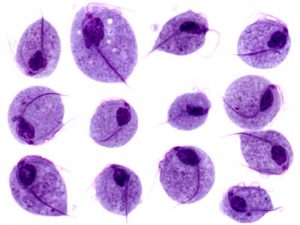

Direct microscopic examination of a wet preparation of sample (vaginal discharge) provides the simplest rapid diagnostic test for vaginalis. It includes detection of pear-shaped trophozoites (only form; there is no cyst form) of T. vaginalis in a wet mount with typical jerky motility.Direct fluorescent Antibody (DFA) stain can be used to visualize the parasite.

Morphological features of Trophozoites:

- Pear-shaped organism with a central nucleus and **four anterior flagella.**2. It has an undulating membrane that extends about 2/3rd of its length.